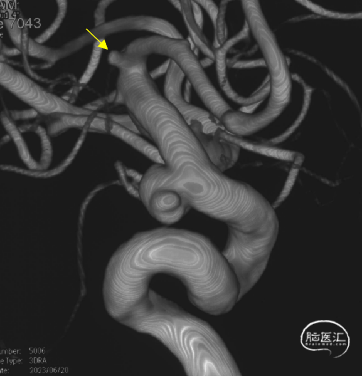

可见一小泡自动脉瘤瘤体上发出

瘤体最大径6.92mm

远端血管直径:3.28mm

近端血管直径:3.98mm

同侧A1可见一小瘤突起

6、Tubridge Plus材料改进后通体显影,可以更好观察支架的贴壁性及术中打开情况,提高释放安全性。